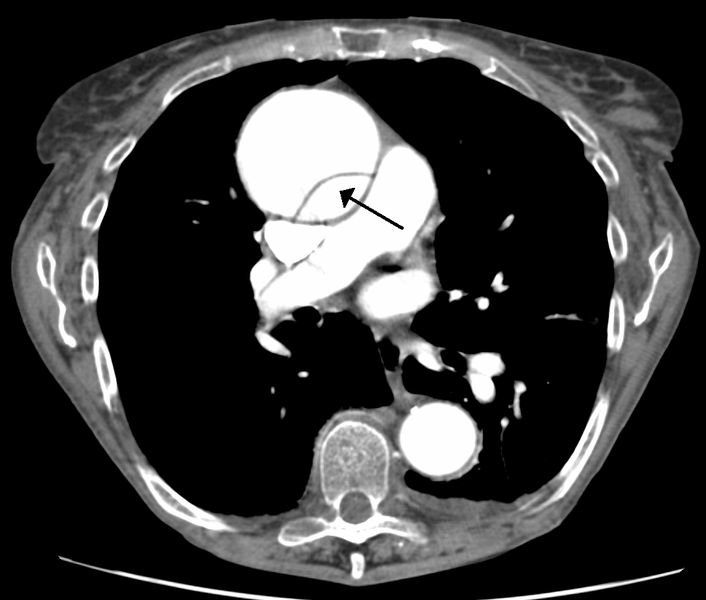

CT chest with contrast of thoracic aortic dissection.

| current | 17:45, 19 May 2016 | ![]() | 1,030 × 875 (352 KB) | Alvarez13 (Talk | contribs) | CT chest with contrast of thoracic aortic dissection. |